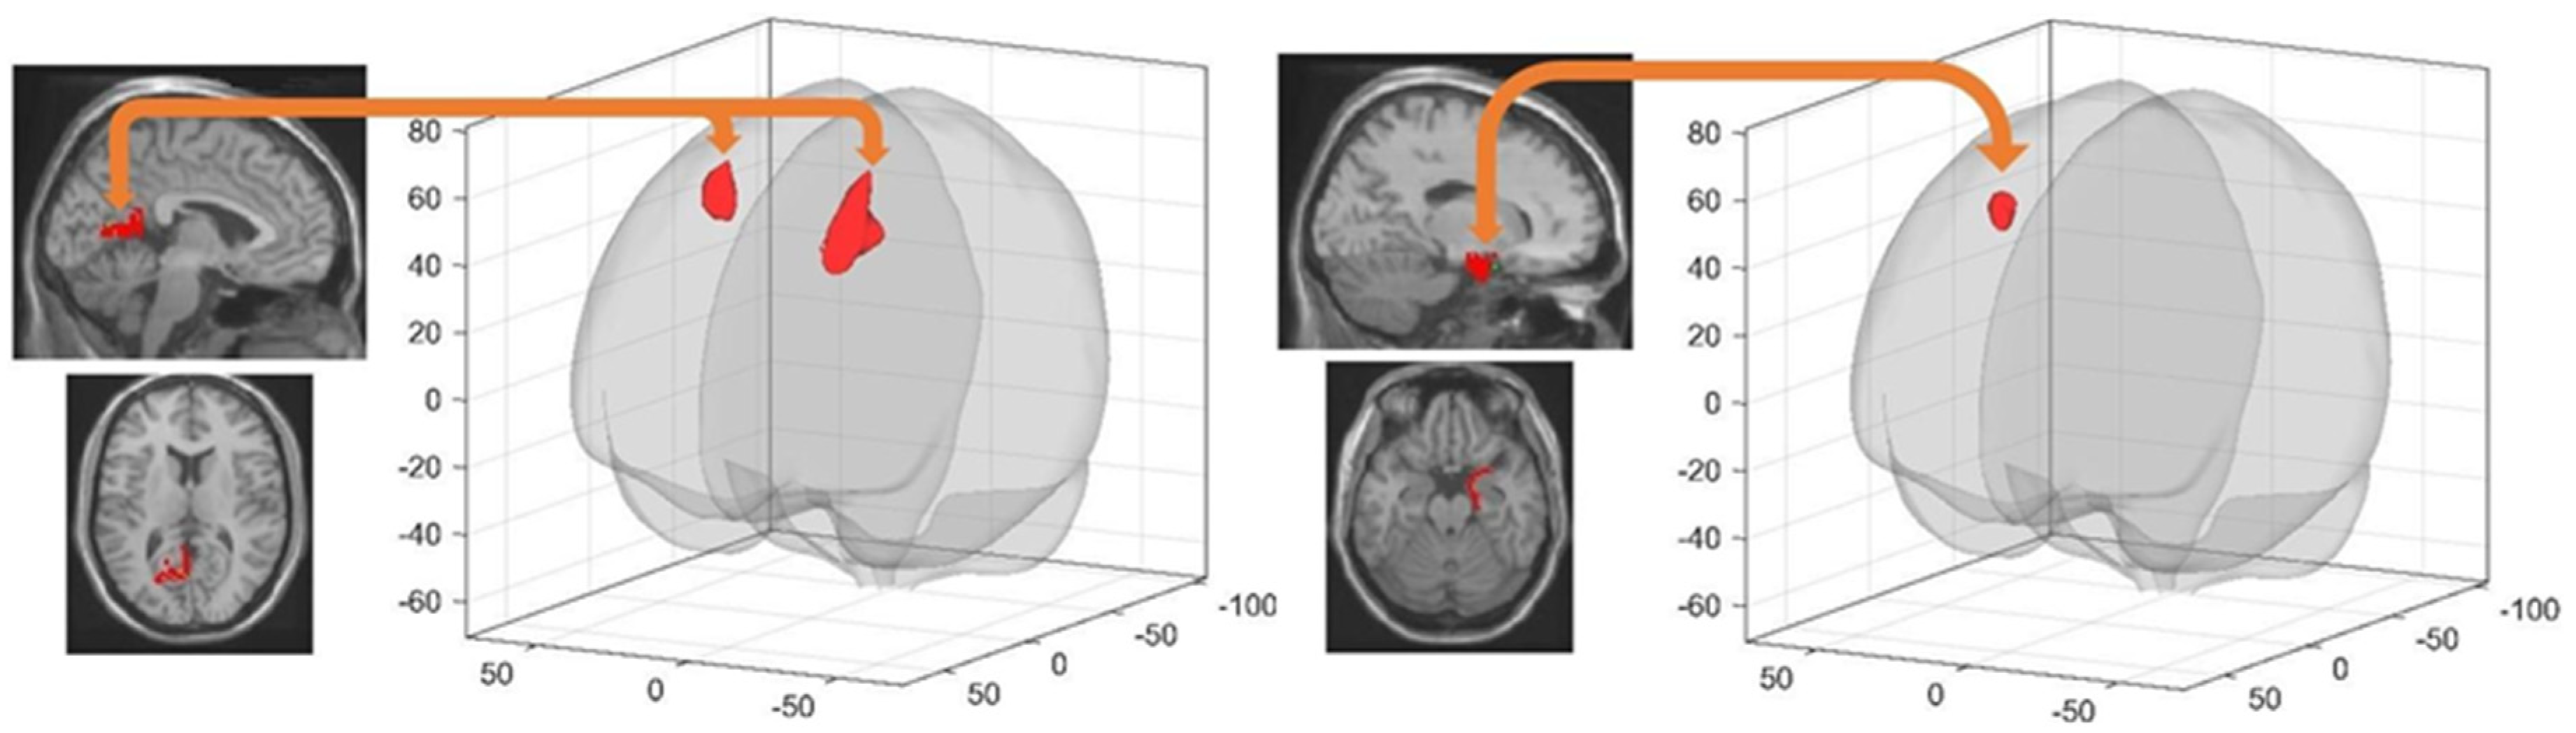

| Left Parahippocampal Gyrus * | Right Precuneus | 6 −60 44 | 330 | 5.09 | 0.000211 |

| Right Precuneus * | Right Middle Frontal Gyrus | 30 4 38 | 324 | 4.26 | 0.000343 |

| Cingulum_Post_L * | Right Supramarginal Gyrus | 58 −34 48 | 232 | 4.57 | 0.000377 |

| Left Hippocampus | Right Middle Frontal Gyrus | 32 4 56 | 247 | 4.95 | 0.002300 |

| Right Entorhinal Cortex | Right Inferiotemporal Gyrus | 52 −18 −24 | 351 | 5.46 | 0.000001 |

| Left Middle Temporal Gyrus | −58 −16 −24 | 401 | 5.02 | 0.000066 | |

| Right Post Cingulate Gyrus | 10 −42 28 | 605 | 4.18 | 0.000197 | |

| Left Entorhinal Cortex | Left lobule VI of cerebellar hemisphere | −30 −40 −34 | 310 | 4.88 | 0.000497 |